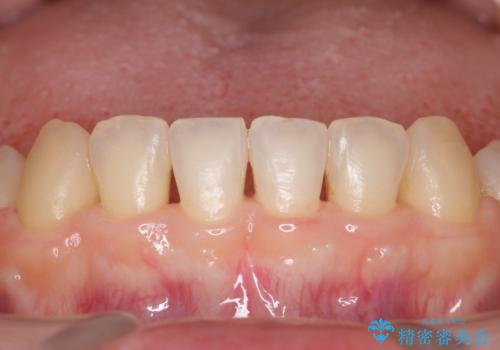

- メンテナンスの際に歯のステインが気になるということで今回はエアフローの機械を使用したクリーニングを行いました。

ステインが付着したままだと歯の表面がざらつき、普段のブラッシング時などに汚れが落ちにくくなります。定期的なメンテナンスの際にPMTC、エアフローを取り入れることをおすすめしております。